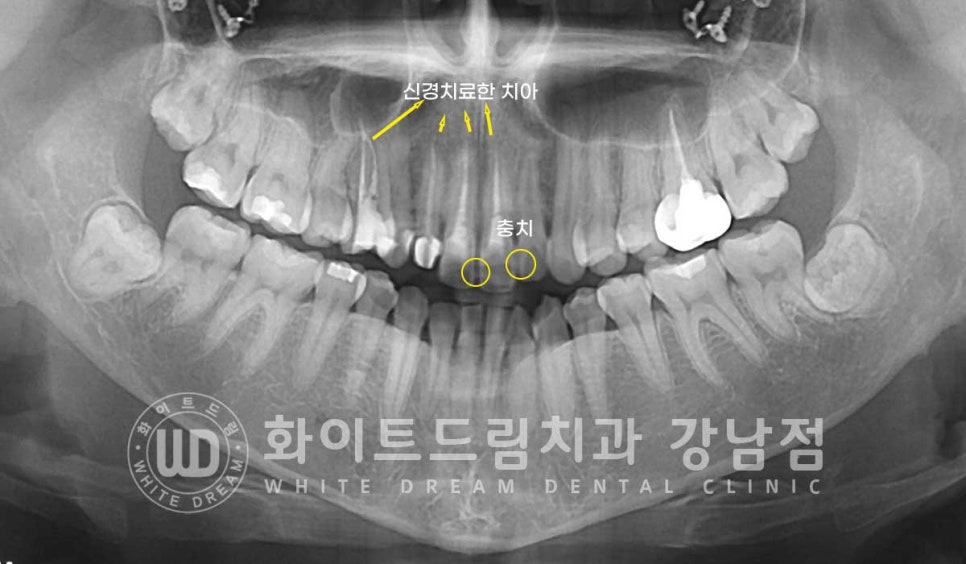

환자분의 x-ray를 보면 신경치료를 받은 치아들이 있는 상태인데

전체 다 크라운치료를 받지 않은 상태입니다.

특히 12번 치아는 이미 변색이 일어난 상태였고

치아 자체가 다른 치아들보다 작은 왜소치였는데요.

신경치료를 받은 치아(14,12,11,21번 치아) → 올 세라믹 크라운으로

변색을 개선하며 치아를 보호해 주기로 했고

초진 치아 검진 시 앞니 11번 치아(mesial 부분)와 22번 치아(distal) 쪽에

충치가 발생한 것이 확인되어 충치 부위 제거 후

보철치료를 진행하기로 했습니다.